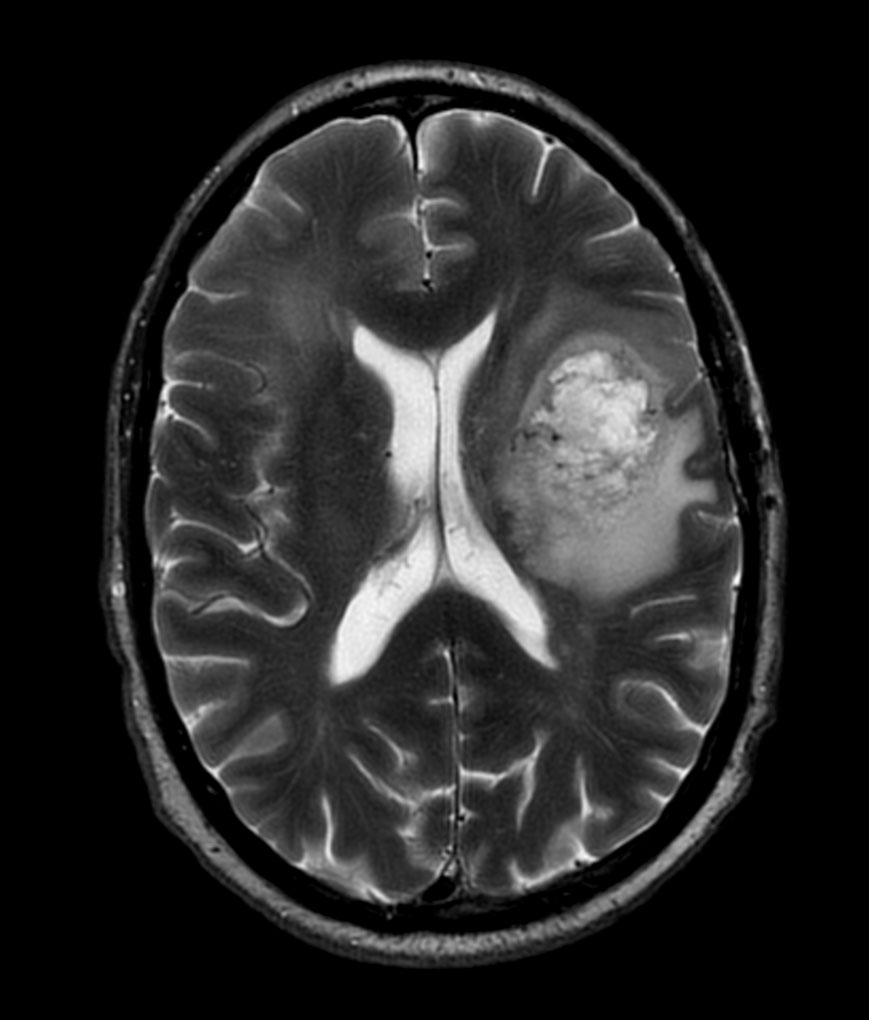

Axial T2w MultiVane XD